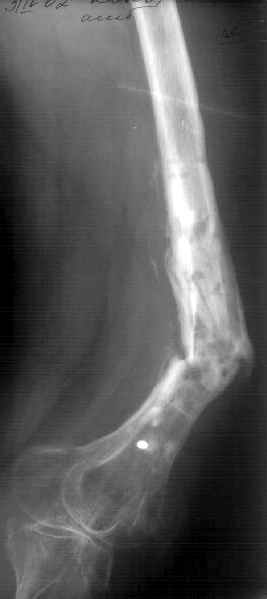

К нам поступила худощавая женщина 48 лет, которой года 2,5 назад был выполнен остеосинтез бедра пластинкой в одной из горбольниц. В сентябре 2001 г. пластинку убрали. Начала разрабатывать движения, ходила с тростью. С января этого года

отмечает усугубление деформации бедра и улучшение движений "в коленном суставе". При осмотре имеетсяподвижность на месте перелома (псевдартроза), больше в сагиттальной плоскости. Рентгенограммы в приложении(фас; профиль). Полностью угол, открытый кзади, под нагрузкой не устраняется. "Сгибается" еще градусов на 30. Ходит с тростью. Надколенник неподвижен, в суставе, видимо, движений нет совсем. В любом случае надо, видимо, начинать с восстановления оси и стабилизации бедра. Как окончательный фиксатор хотелось бы использовать интрамедуллярный стержень. Можно ли в данном случае устранить угол одномоментно? Или лучше дозированно? Нужна ли костная пластика местно? Не стоит ли пойти на мобилизующую операцию в один этап? Если да, то какую?Может быть, есть еще какие-то моменты, которые следует учесть?Спасибо заранее.-- Best regards, Alexander N. Chelnokov

Клинико-рентгенологически - замедленная консолидация.

Если инфекция присутствует (вполне возможно, судя по рентгенограмме), резекция инфицированной, некротизированной кости, замещение образовавшегося дефекта с помощью транспорта костного блока в аппарате.